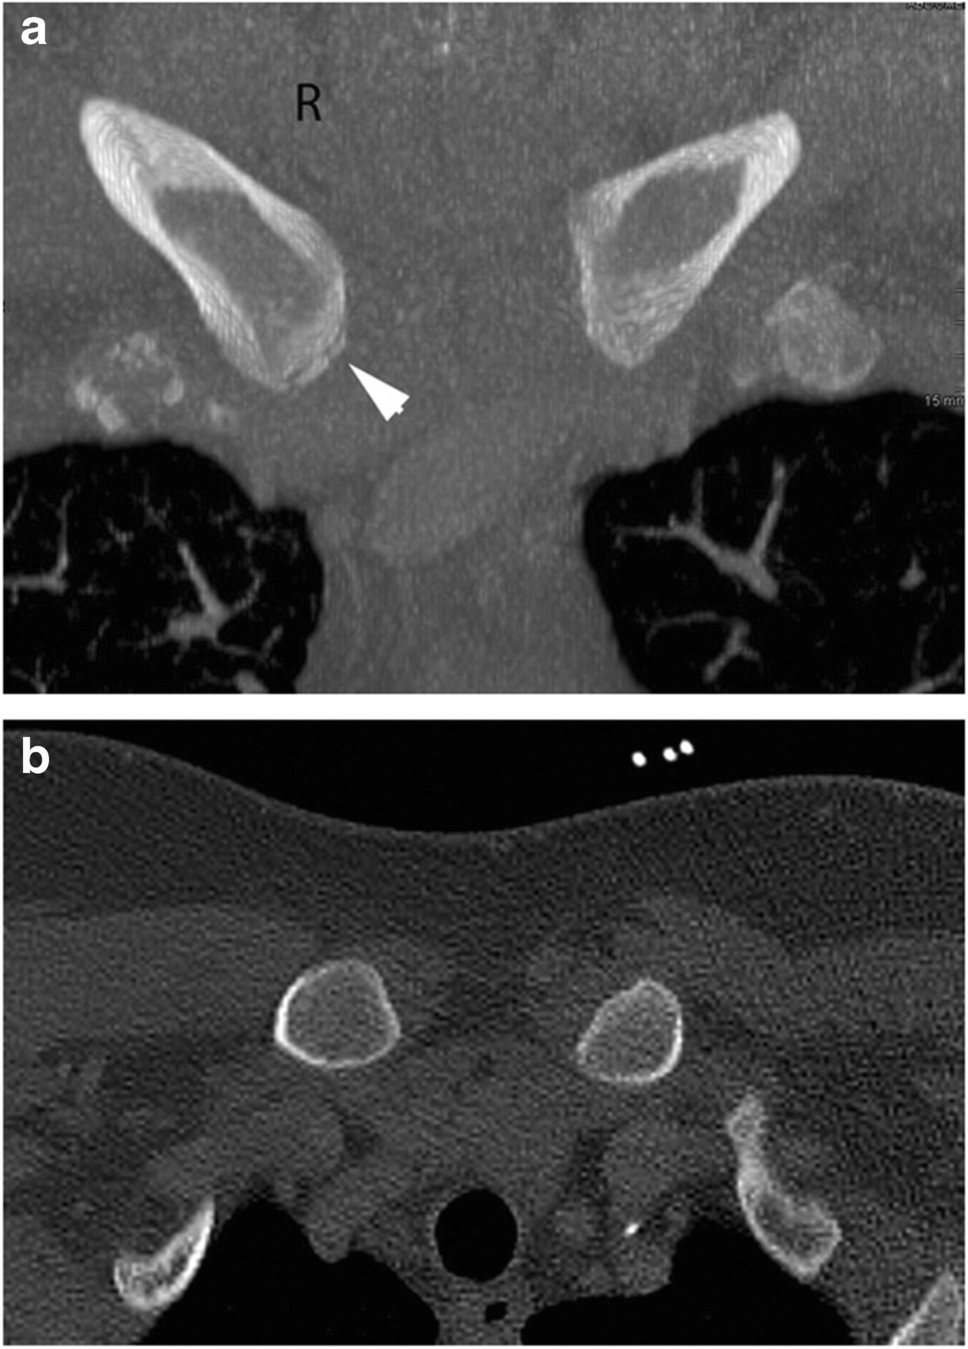

In this study, only symmetrical, bilateral ossification of stage 4 achieved a specificity and positive predictive probability of 100%. If, on the other hand, only the unilateral attainment of stage 4 is used as a criterion, a specificity of only 98.6% is achieved. In this study population, one subject with a chronological age < 21 years (exact age: 20 years and 10 months) stood out, who exhibited stage-4 ossification on one side and stage 3c on the other side. An expert forensic assessment taking into account only the more advanced side would have diagnosed an age over 21 years. This subject was a heavy labourer (lumberjack) and very muscular, which may explain the premature constitutional skeletal maturity. A possible use of anabolic substances cannot be excluded (Fig. 3a/b).

Fig. 3

a/b Male subject aged 20 years and 10 months. The stages of maturity of the medial clavicles were 3c on the right and 4 on the left (CT MIP projection). He is the only study participant who reached maturity stage 4 before the age of 21. a Coronal plane. b Axial plane